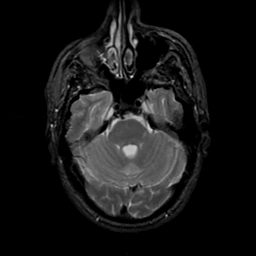

MR Study #22, December 1, 1991 -- Slice #14

[Home][Help][Clinical][Tour 1][Tour 2] Slice 14